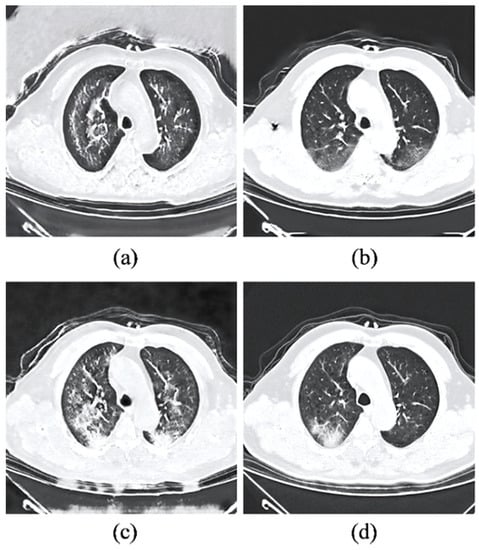

3.7. External Validation on Different Clinical Cases

- Perceptual realism and quality. While the perceptual quality can be evaluated using the standard FID metric, the actual reality of the synthetic COVID-19 remains challenging due to the domain knowledge requirement. With the help of an experienced radiologist, the Visual Turing Test reveals a promising result achieved by the synthetic images for generating radiography findings of GGO, which is consistent with the real COVID-19 CT images. Furthermore, exhaustive experiments demonstrate the consistent adversary correlation between image diversity and perceptual quality due to the underlying property of the stacked residual dropout, which induces latent space stochasticity and simultaneously encourages a more unconstrained space of image mapping. Thereby, a larger magnitude of stochasticity can generate additional noise artifacts that could be detrimental to the overall perceptual quality and realism of the images. The impact of the adversarial relationship between perceptual quality and image diversity is addressed by a reduced dropout rate at higher dimensional latent spaces. As a result, drastic improvement in the perceptual quality was noticed without affecting the significance of synthetic features generated on the output images. Furthermore, the sRD-GAN also demonstrated superior performance in terms of perceptual quality compared to other GAN baselines, where images generated from the GAN are distorted by a significant amount of noise artifacts. In contrast, the images generated from CycleGAN and one-to-one CycleGAN models failed to effectively eliminate the noise artifacts.

- Effective noise reduction. The comparison between the images generated with and without pixel consistency and cycle consistency reveals the distinctive differences between the consistency losses in the image translation task. In particular, the proposed adaptive pixel consistency loss demonstrated superior performance in reducing the noise artifacts of the synthetic images. The effectiveness of the noise reduction is due to the strong connection enforced by the pixel consistency loss, which encourages the output image to be similar to the input image. Moreover, the adaptive setting of the pixel consistency loss addresses the problem of the diminished magnitude of the translated GGO features caused by the pixel consistency constraint. A possible explanation is that the conditional weight updates of the loss are based on the generator’s performance. The superior performance of the adaptive setting of the pixel consistency and its high effectiveness in reducing noise artifacts is also demonstrated on other GAN baselines.